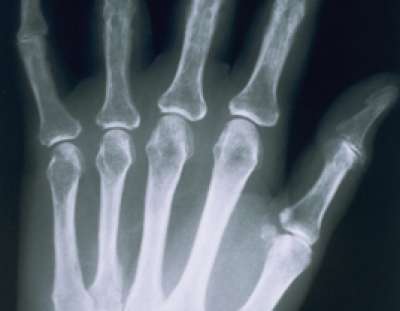

ونوه الى أن حيوان السمندر يستعيد أرجله المقطوعة خلال أسبوعين حيث تنمو الخلايا والأنسجة في جسمه تلقائيا .. وأوضح عطالله انه باستطاعة الإنسان ان يستعيد أعضاء جسمه من خلال التكنولوجيا المتطورة التي يمتلكها .. وان العلم أثبت بأن نظام العظام في جسم الإنسان يتجدد تلقائيا بصورة كاملة خلال عشر سنوات .